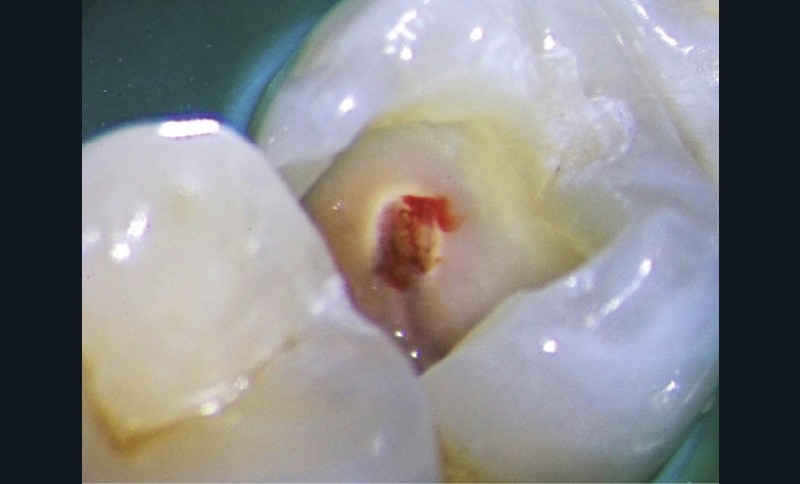

Le laser Er:YAG va permettre une élimination des débris en surface, une stérilisation, avec comme irrigation de l’eau stérile [36] et en coupant le spray, une hémostase avec la formation d’une couche de coagulation [37] propre à la formation d’un pont dentinaire au contact du biomatériau, qui peut être bio-actif, tel que la Biodentine (Septodont) (fig. 6a à d).

Protocole opératoire : sous anesthésie, une cavité suffisante à recevoir le biomatériau (2 à 3 mm) sous champ opératoire est réalisée. La désinfection au laser Er:YAG (40 mJ ; 20 Hz) sous spray, pendant 20 secondes, est alors mise en œuvre. S’en suit éventuellement une coagulation de 3 secondes, en coupant le spray, puis la mise en place du biomatériau Biodentine (Septodont). Il sera ensuite recouvert d’un matériau de restauration adéquate.